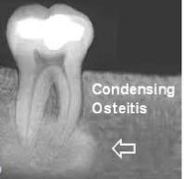

outline condensing osteitis

condensing osteitis

diffuse radiopaque lesion representing a localised bony reaction to a low grade inflammatory stimulus usually seen at the apex of the tooth

increased mineralisation around apices of teeth

stimulus will often have been present for a long time